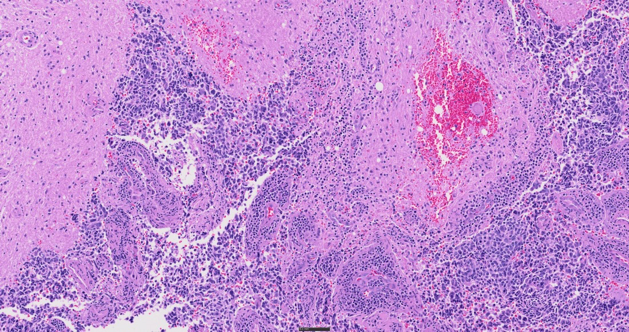

H&E stained tissue, 40X

Supporting up to six high-performance X Line™ objectives and featuring True Color LED illumination and color-corrected camera profiles, the SLIDEVIEW VS200 system delivers clarity in whole slide images. The scanner is engineered for consistent reproduction of sample and stain characteristics, minimizing the need for rescans and supporting efficient diagnoses.

Discover more details in your samples with five imaging modes—brightfield, polarization, fluorescence, darkfield, and phase contrast—and the ability to combine multiple techniques in a single scan. This flexibility offers a wide range of possibilities to observe histology and cytology samples, from routine pathology to complex molecular characterization of cancerous tissue.